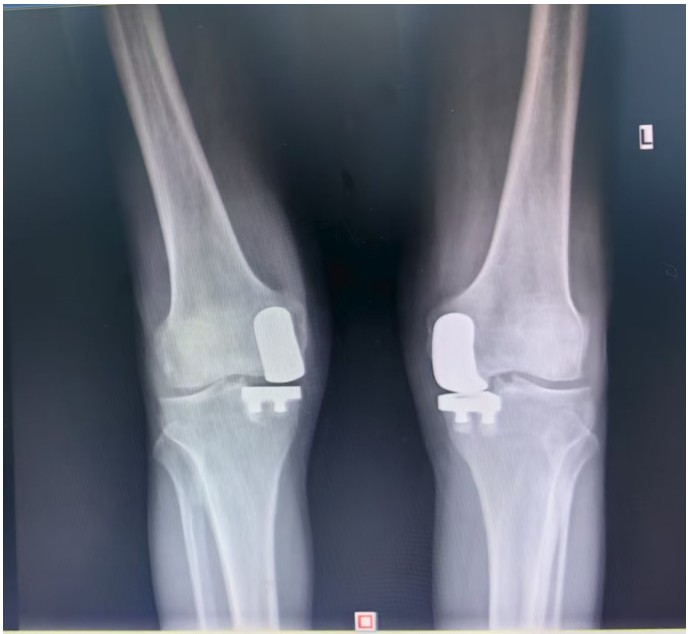

據(jù)了解,患者1年前無(wú)明顯誘因出現(xiàn)雙膝關(guān)節(jié)疼痛,以右側(cè)膝關(guān)節(jié)為主,近5個(gè)月來(lái)雙膝關(guān)節(jié)疼痛明顯加重,不但日常行走困難,生活質(zhì)量更是受到極大影響。經(jīng)多家醫(yī)院治療效果均不理想,了解到衡陽(yáng)市中心醫(yī)院關(guān)節(jié)外科在關(guān)節(jié)置換領(lǐng)域擁有豐富的臨床經(jīng)驗(yàn)和良好的患者口碑,毅然決定赴衡求醫(yī)。醫(yī)生發(fā)現(xiàn)患者雙膝關(guān)節(jié)已有內(nèi)翻畸形,關(guān)節(jié)內(nèi)側(cè)骨性膨大,X線提示雙膝退行性病變,雙膝內(nèi)側(cè)間隙明顯狹窄,手術(shù)為最佳治療方式。為了達(dá)到根治目的,羅湘平主任醫(yī)師、彭健副主任醫(yī)師為患者進(jìn)行了詳細(xì)查體及綜合評(píng)估,術(shù)前組織開(kāi)展多學(xué)科討論(MDT)。考慮到易叔叔的膝關(guān)節(jié)骨關(guān)節(jié)炎僅局限于內(nèi)側(cè),外側(cè)間室軟骨良好,若采用全膝關(guān)節(jié)置換術(shù)會(huì)將失去正常關(guān)節(jié)間室的軟骨與韌帶,創(chuàng)傷較大,便為其制定了右膝關(guān)節(jié)單髁置換手術(shù)治療方案。在充分完善術(shù)前準(zhǔn)備后,羅湘平主任、彭健副主任醫(yī)師團(tuán)隊(duì)為患者實(shí)施了右側(cè)膝關(guān)節(jié)單髁置換術(shù)。手術(shù)過(guò)程順利,團(tuán)隊(duì)?wèi)?yīng)用微創(chuàng)術(shù)式(MIS)及“精準(zhǔn)間隙平衡技術(shù)”,最大程度減少了手術(shù)創(chuàng)傷,為術(shù)后快速康復(fù)奠定了堅(jiān)實(shí)基礎(chǔ),術(shù)后第二天即可借助助行器下地活動(dòng)。6天后團(tuán)隊(duì)順利為患者實(shí)施了左側(cè)膝關(guān)節(jié)單髁置換手術(shù)。目前,易叔叔在關(guān)節(jié)外科醫(yī)護(hù)團(tuán)隊(duì)的精心指導(dǎo)和康復(fù)治療下,恢復(fù)情況良好,雙側(cè)膝關(guān)節(jié)活動(dòng)度輕松達(dá)到90°,膝關(guān)節(jié)功能顯著改善,能夠獨(dú)立下地行走,對(duì)手術(shù)效果非常滿意,已于9月10日順利出院。

羅湘平主任介紹,膝單髁置換術(shù)是針對(duì)膝關(guān)節(jié)單側(cè)間室病變的微創(chuàng)手術(shù),該術(shù)式通過(guò)置換單側(cè)股骨或脛骨受損軟骨表面,保留交叉韌帶及正常骨質(zhì)結(jié)構(gòu),因創(chuàng)傷小、恢復(fù)快被稱為膝關(guān)節(jié)置換中的“補(bǔ)牙”技術(shù),適用于單間室骨關(guān)節(jié)炎且韌帶功能完整的患者。膝關(guān)節(jié)單髁置換為特定的膝關(guān)節(jié)疾病患者提供了一種較為理想的治療選擇,它以較小的手術(shù)創(chuàng)傷、良好的術(shù)后功能恢復(fù)效果,幫助患者緩解疼痛,恢復(fù)正常的生活和活動(dòng)能力。